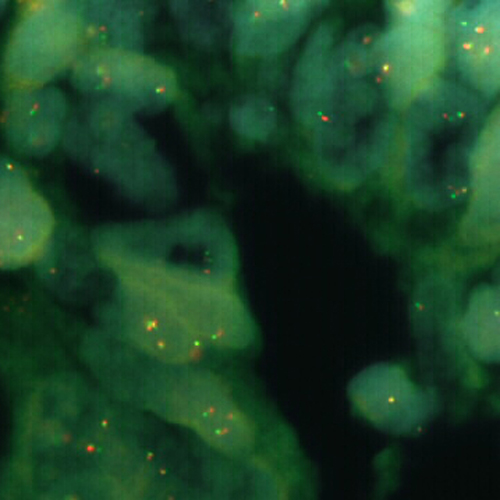

FUS (16p11.2) Break probe hybridized to liposarcoma material.

RUO - FUS Break (16p11.2)

The fused in sarcoma (FUS) gene was originally shown to be rearranged in myxoid liposarcomas harboring a t(12;16)(q13;p11) translocation. FUS has also been shown to be involved in other recombinations: with ERG in acute myeloid leukemia carrying a t(16;21), with ATF1 in band 12q13 in angiomatoid fibrous histiocytoma, and with CREB3L2 in fibromyxoid sarcoma. A break or split probe for FUS is best used to analyze translocation of the FUS (16p11) gene on formalin fixed paraffin embedded tissue for routine clinical diagnosis. The FUS (16p11) Break probe is optimized to detect translocations involving the FUS gene region at 16p11 in a dual-color, split assay on metaphase/interphase spreads and paraffin embedded tissue sections.